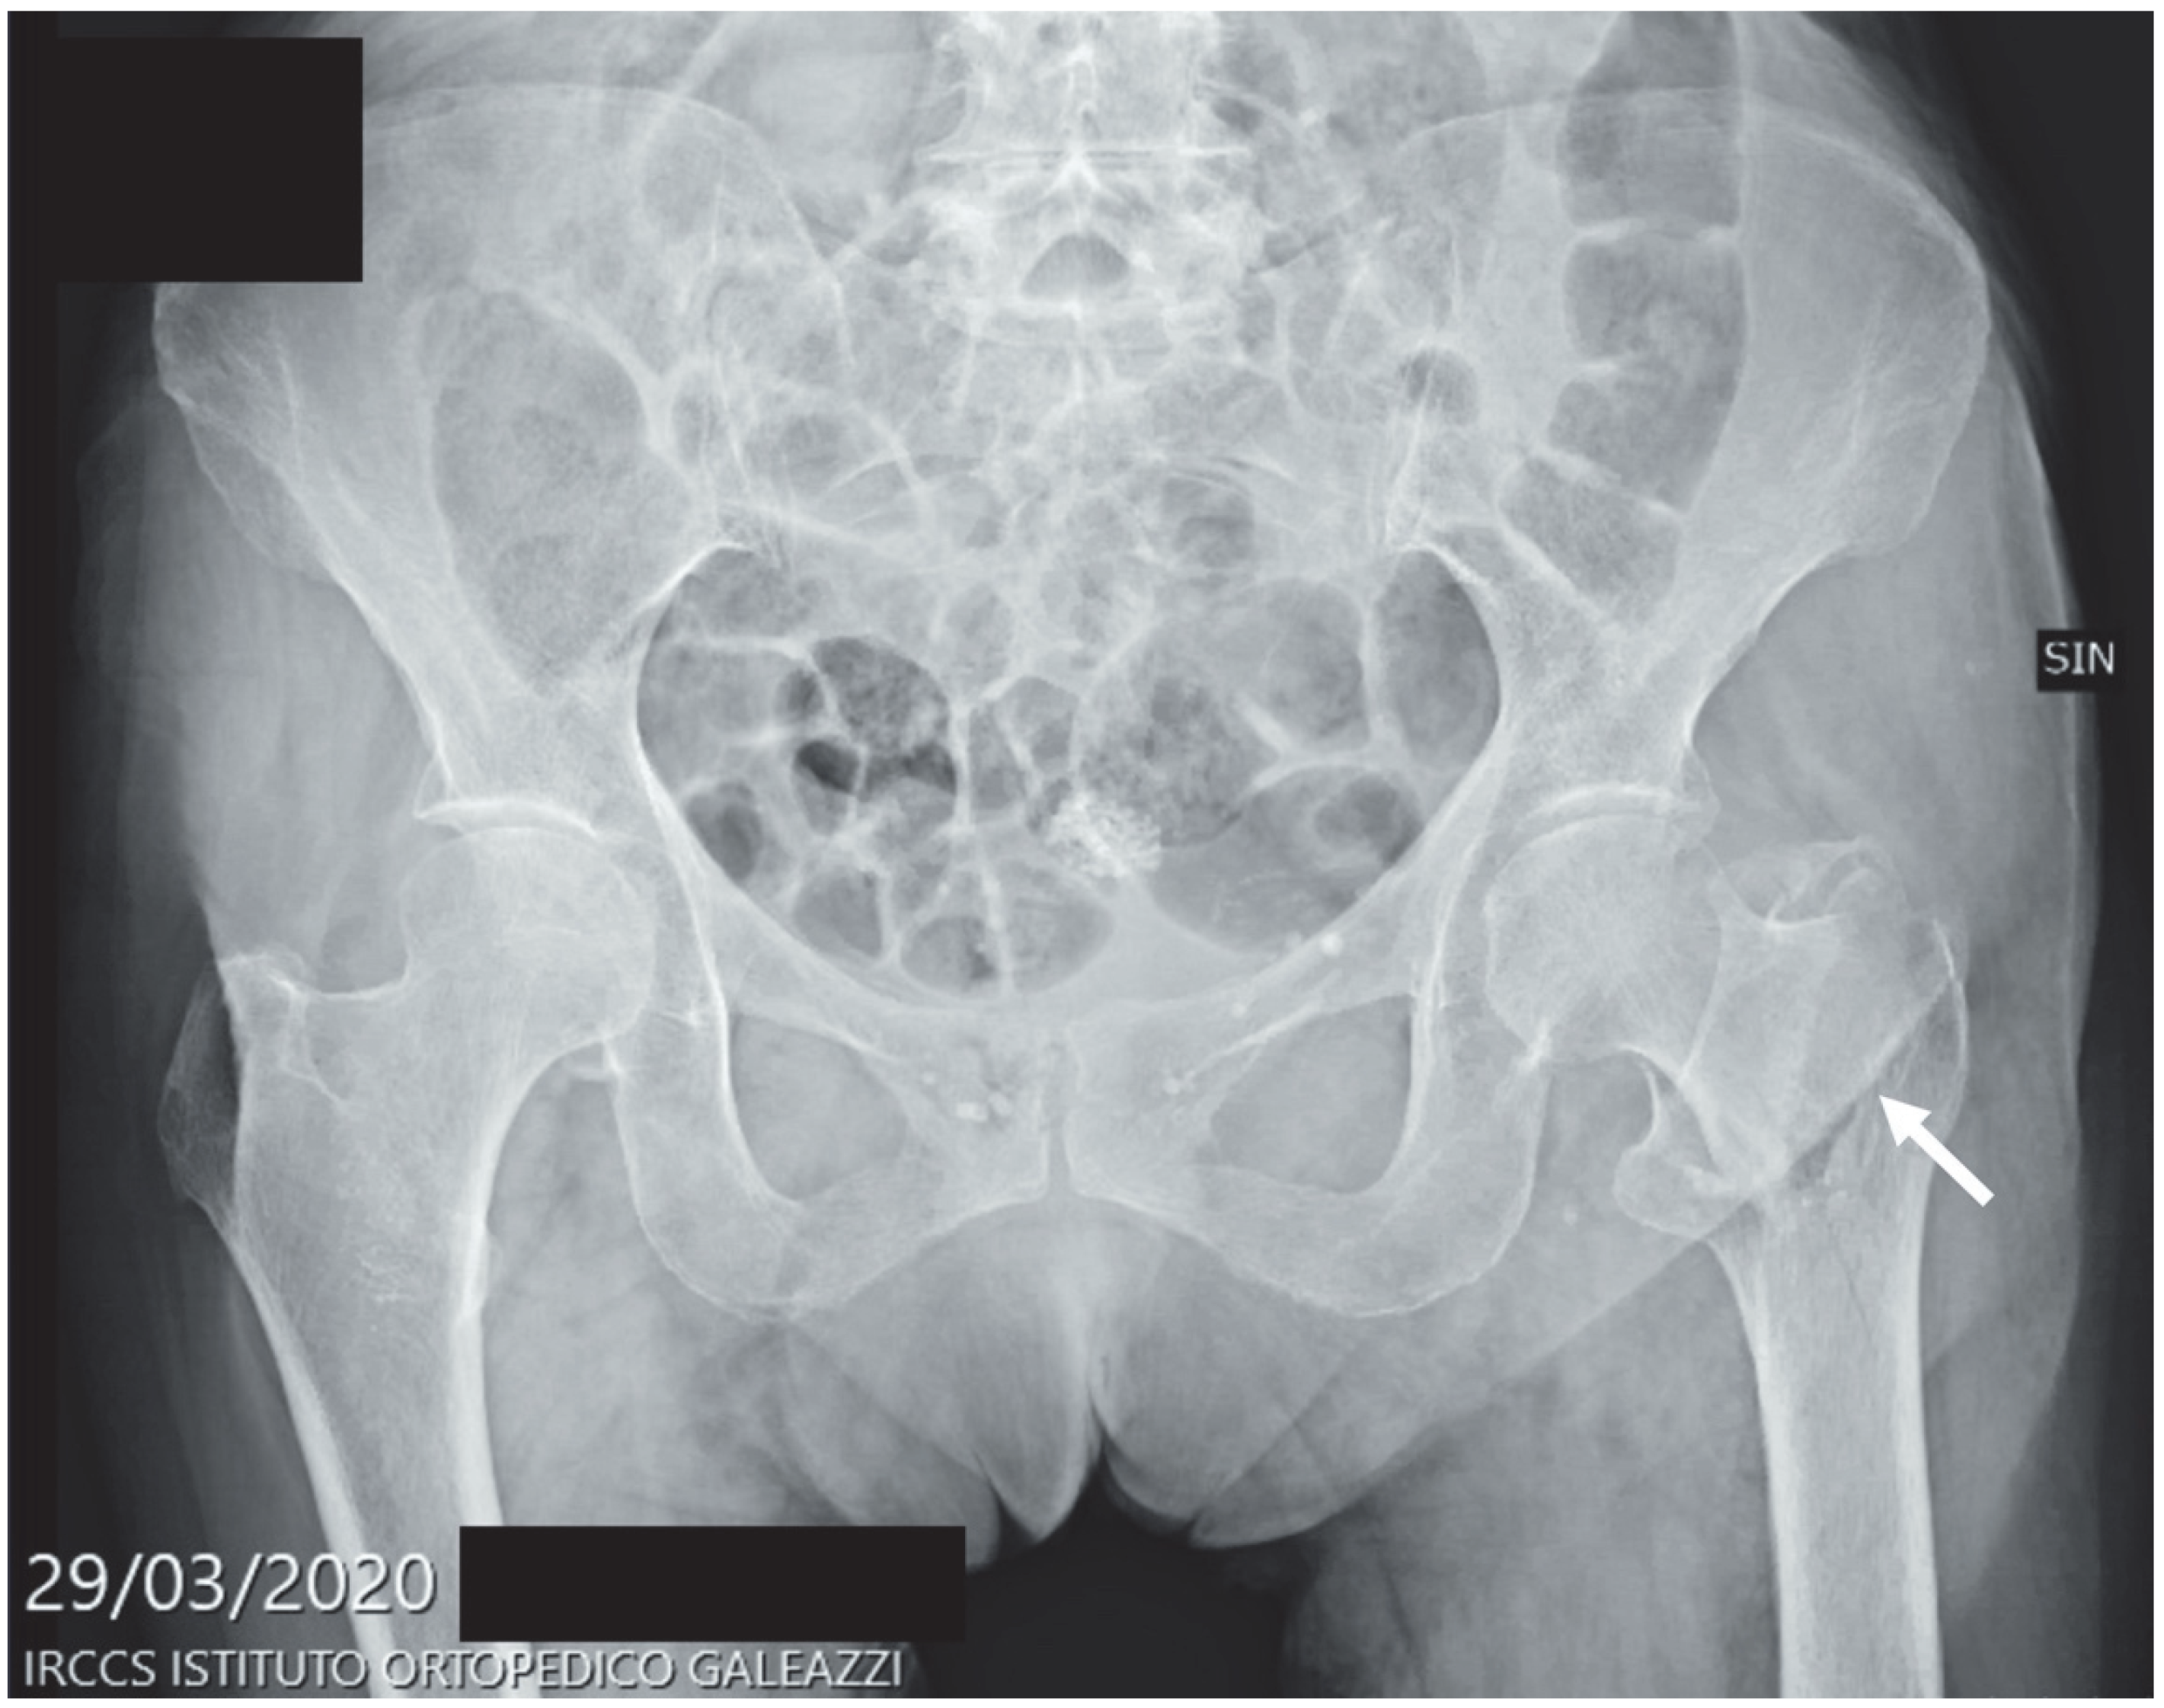

| Proximal femoral fractures | 179 | 19.7% | 262 | 16.7% | 77 | 5.4% | 99 | 5.9% |